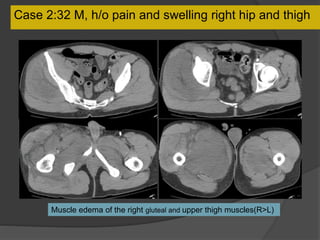

Case 2:32 M,h/o pain and swelling right hip and thigh

Case 2:32 M, h/o pain and swelling right hip and thigh

Muscle edema of the right gluteal and upper thigh muscles(R>L)

Case 2 Diagnosis: Rhabdomyolysis

Nonspecific clinical and laboratory

syndrome

Severe muscle injury due to trauma,

severe exercise, extrinsic pressure,

ischemia, burns, toxins, autoimmune

inflammation

Edema may progress to myonecrosis,

hematoma and infection or

compartment syndrome.

Elevated creatine kinase, pigments in

urine and hematuria

Fasciotomy and on aggressive IV

fluids for rhabdomyolysis

Drug overdose, found unconscious and

trapped between the toilet seat and wall

RadioGraphics July 2004